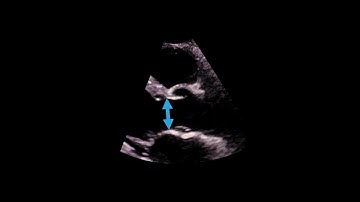

Hot Tips - Calculating the Aortic Valve Area Using the Continuity Equation